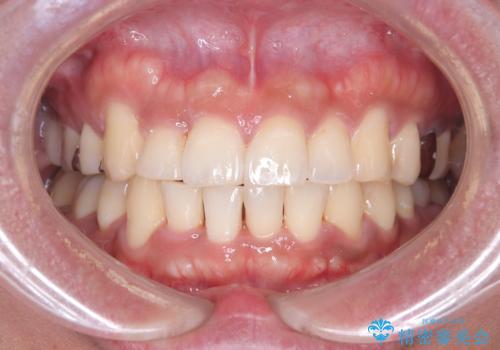

【ワイヤー矯正】八重歯と下の歯の凸凹を治したい

- 主訴:右上の八重歯と、下の歯の凸凹を治したい

上顎右側第一小臼歯と下顎右側第一小臼歯を抜歯しワイヤー矯正を行いました。

右側2級、左側1関係だったため、右側上下第一小臼歯を抜歯し、ワイヤー矯正を行いました。